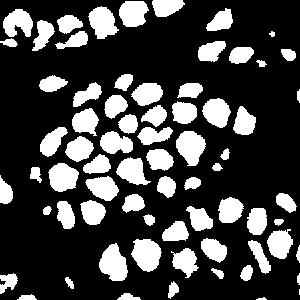

An example is shown in Fig. 2 to illustrate the masks in different rounds of self-training. The foreground nuclei annotation (green pixels) is kept unchanged during the iterations while the background area (pixels in black) grows up gradually. In the third round, the background has high accuracy and the ignored pixels (orange) are almost all nuclei.

(a) image

(b) round 1

(c) round 2

(d) round 3